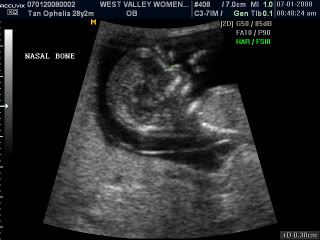

Our little beanie's face, can you spot his little nose? I hope it looks like daddy's more pointy hehe, mine's bigger than daddys!!!